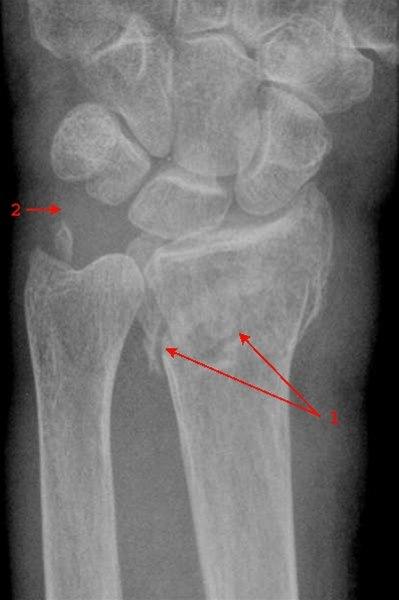

Brudd i nedre del av radius, mindre enn 4 cm fra nedre ende av beinet, betegnes på fagspråket som distalt radiusbrudd eller fractura radii typica. Denne bruddtypen kan medføre at de to bruddendene spriker eller blir forskjøvet i forhold til hverandre, men bruddet kan også være uten forskyvning av bruddendene. I unntakstilfelle kan bruddet skade nerver som ligger nær.

Brudd i håndleddet er den vanligste bruddskaden som forekommer. Bruddtypen er hyppigst hos eldre kvinner, men det er heller ikke uvanlig hos yngre personer. Cirka 90 prosent av bruddene innebærer at det ytterste bruddstykket er skjøvet opp (dorsalt, mot håndryggssiden) - denne bruddtypen kalles også Colles brudd (se tegningen over).

Røntgenbilder tatt forfra og fra siden bekrefter diagnosen (se over). Man ser etter feilstillinger, om det er brudd som innbefatter selve håndleddet, om det er ujevnheter i leddspalten, eller om det foreligger andre beinskader.